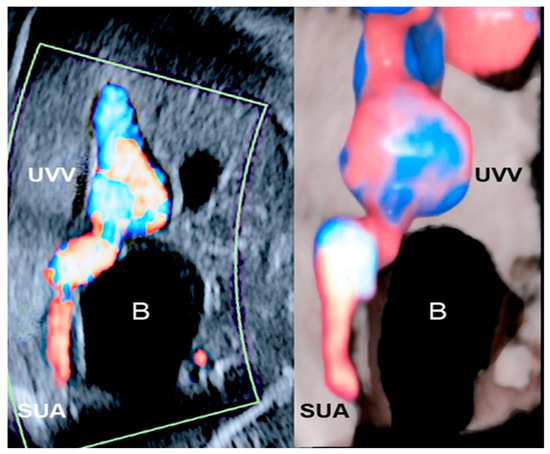

3.4. Single Umbilical Artery

3.5. Supernumerary Vessels